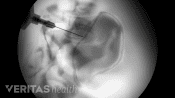

Then, using fluoroscopy dye and X-rays to assist in guiding the injection, a needle is inserted into the sacroiliac joint to deliver medicine directly to the source of pain.